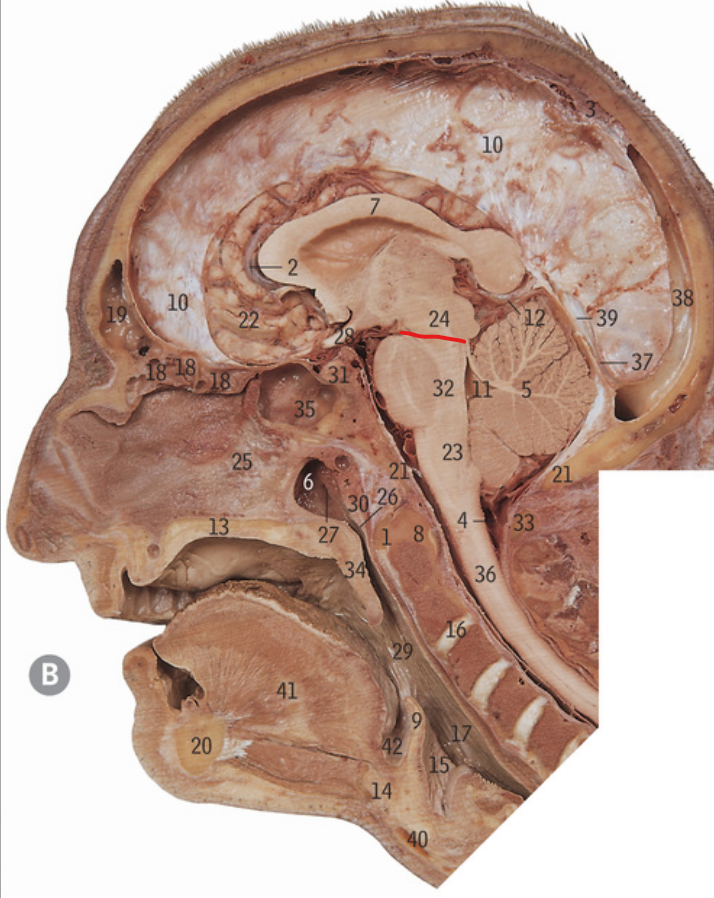

24

Midbrain

32

Pons

23

Medulla oblongata

4

Clivus

5

Cerebellum

10

Foramen magnum

Cerebral aqueduct

4th/fourth ventricle

Floor of fourth ventricle

Middle cerebellar peduncle

2

Cisterna magna

What is the line referring to

Pontomesencephalic junction